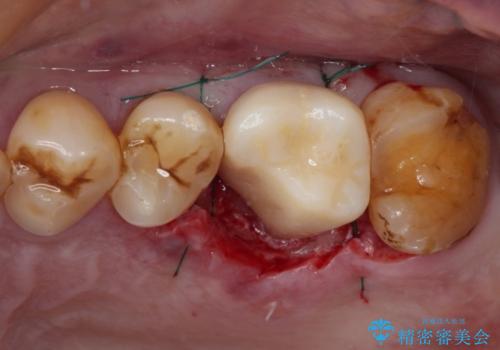

咬合面に大きな修復物が入っており、その境目から破折し、歯肉の内側の歯根にまで破折が及んでいました。

残念ながら神経組織が露出しており、根管治療が必要となっていたため、まずは根管治療を行うこととしました。

根管治療後に、歯根にまで及んでしまった破折部分を適切な位置に変更するため、歯槽骨の削除を伴う外科処置を行い、その後補綴治療を行うこととしました。